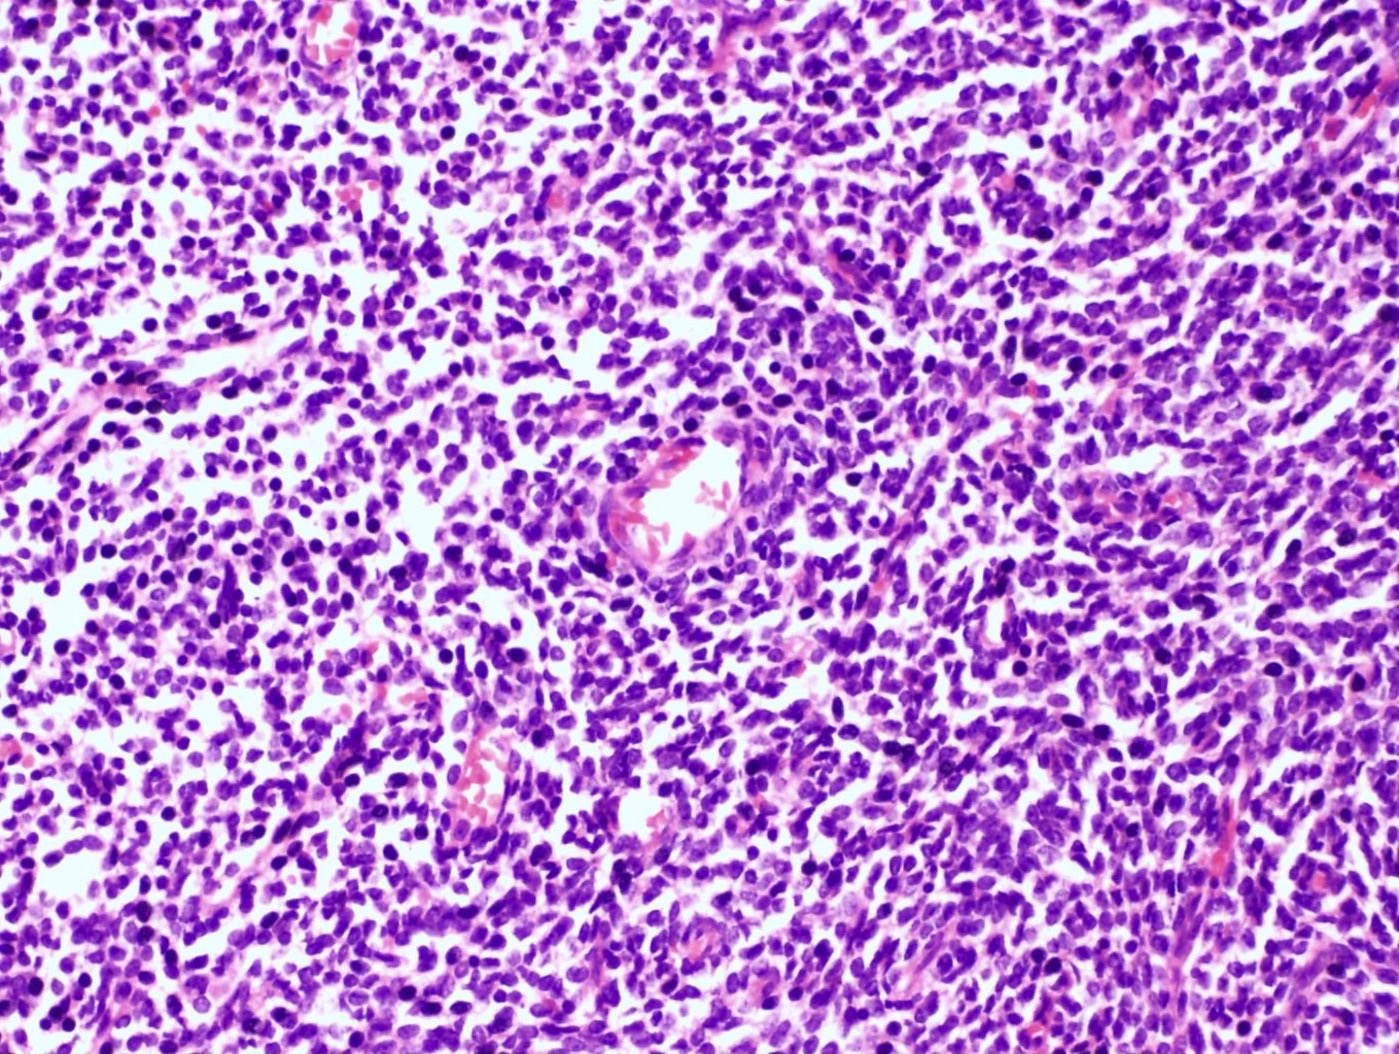

Microscopic (histologic) description

- Irregular cellular islands, forming permeative tongue-like pattern of myometrial invasion with frequent vascular invasion

- Monotonous oval to spindle cells with minimal cytologic atypia, vesicular chromatin and scant cytoplasm

- Mitotic count is usually low (< 5/10 high power fields), necrosis is usually absent

- Tumor cells may whorl around delicate arteriolar type vessels, reminiscent of proliferative phase endometrial stroma

Microscopic (histologic) images

Contributed by Elizabeth Kertowidjojo, M.D., Ph.D., M.P.H. and Ayse Ayhan, M.D., Ph.D.